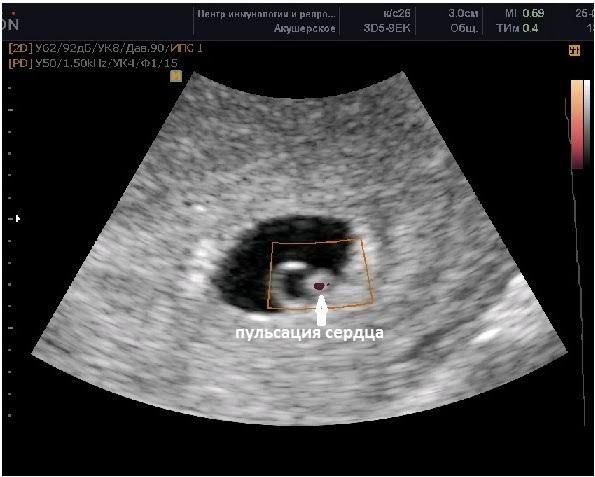

В 6 недель при здоровой беременности будет эмбрион в виде такого кольца и там уже будет биться сердечко.